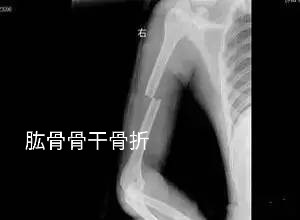

四、肱骨骨折X线图

肱骨骨折根据发生部位的不同分为肱骨外科颈、肱骨干、肱骨髁上、肱骨髁间、肱骨外髁、肱骨内上髁。